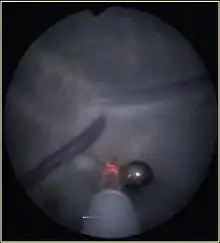

Методика заключается в фетоскопическом (через тончайшую оптическую систему) введении лазерного проводника сквозь переднюю брюшную стенку матери в полость матки под контролем УЗИ. Поверхностные анастомозы на плаценте, по которым кровь перетекает от одного плода другому — коагулируется лазерным лучом мощностью 35 — 60 Вт под контролем зрения (на мониторе). Данная процедура не вызывает нарушения кровотока плодов, поскольку крупные плацентарные и пуповинные сосуды не затрагиваются.